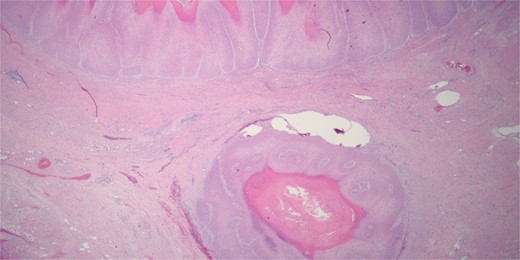

The patient underwent serial debridements and wound VAC changes until final pathology was confirmed as VC arising in association with GCA measuring 28 × 13 × 6 cm (Fig. 3) without any lymphatic or vascular invasion. The tumor had pushing borders without any invasion, which distinguishes it from conventional invasive SCC (Fig. 4).

Histologically the specimen was a well-differentiated squamous cell carcinoma with pushing borders without any infiltrative invasion, specifically distinguishing it from conventional invasive squamous cell carcinoma.